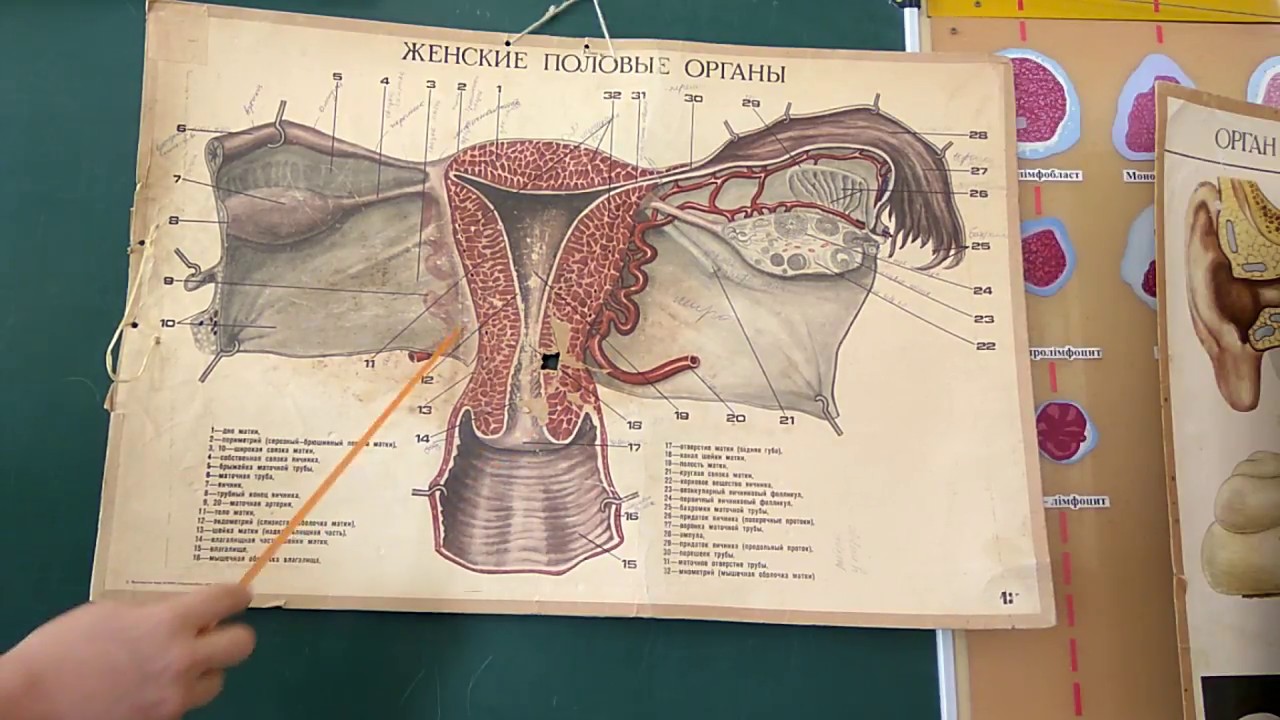

Тайны женского организма: здоровье и понимание

Раздел: Экспозиция интеллекта